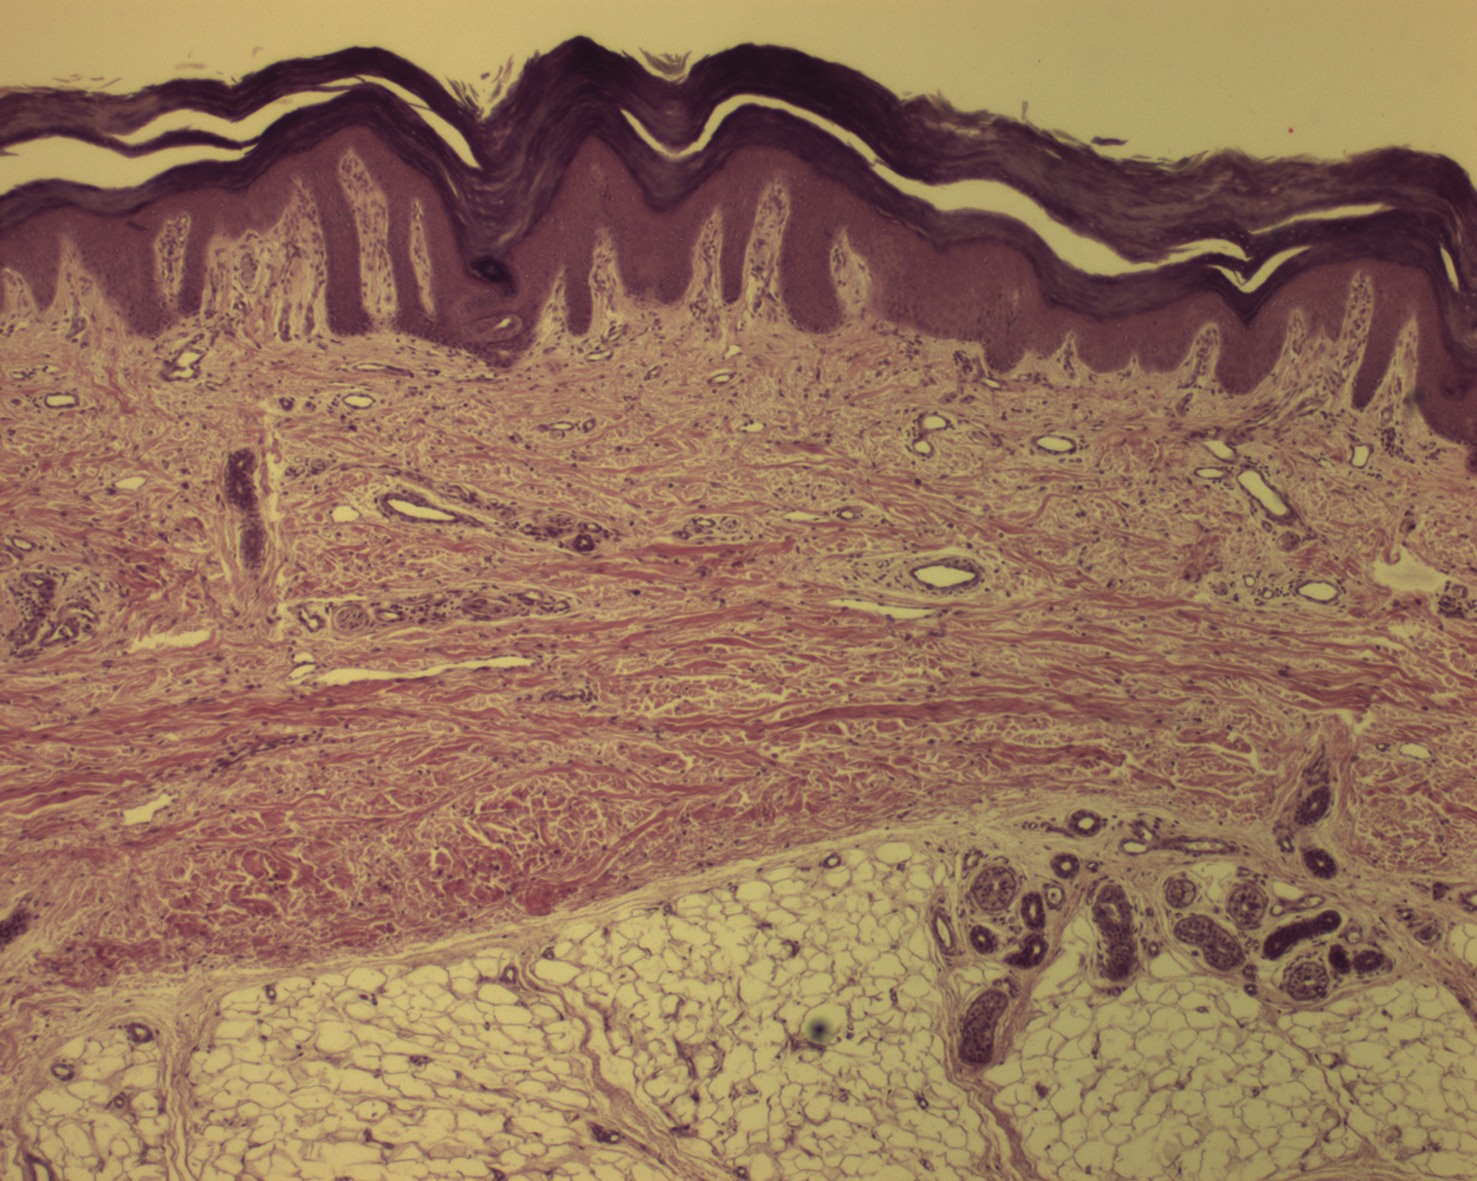

In order to use BAT products successfully, it is important to have a strong understanding of the fundamental characteristics of skin. Within the context of wound healing, there are four important components to consider. These components are the epidermis, dermis, hypodermis (subcutaneous adipose tissue) and underlying tissue. The epidermis is the most superficial component of skin. It has no direct vascular supply and sloughs continuously. The dermis is often regarded as the most important skin component to wound healing and this is where clinicians look for granulation tissue. As a key marker for healing potential, granulation tissue is literally a collection of newly formed vascular buds. As part of the standard of care, wound bed debridement involves removing nonviable tissue and inhibitory factors such as proteases and collagenases. The mechanical action of debridement disrupts the vascular buds at the surface of the wound base, causing bleeding. A bleeding wound base often indicates a viable base, which is a positive predictor for wound healing.11,12 It is also important to understand that adipose tissue and other deep tissues (fascia, tendon, bone and muscle) have the potential to form granulation tissue. Accordingly, proper debridement of these deep wound components can be essential to overall healing potential.11 The skin contains important growth factors (e.g. VEGF, PDGF) that stimulate tissue repair and angiogenesis during the process of wound healing. Bioengineered alternative tissue products generally stimulate these processes in the wound bed or can often serve to deliver growth factors extrinsically when one applies them to the wound. Some BATs contain living fibroblasts and keratinocytes in addition to growth factors. These living cell components can play an important role through the continued production of growth factors after their delivery to the wound bed. Another key role of BAT products is the matrix component, which can assist in rapid wound ingrowth and building wound integrity by providing a temporary scaffold. When selecting a particular BAT product, it is important to keep in mind the different layers of tissue and their architecture as described above. In many cases, one can choose a specific product to match the wound depth and nature. When clinicians use BAT products incorrectly, the results have a lesser degree of predicted success and the clinician may wrongly conclude that the product is ineffective or inferior. Proper selection of BAT products increases the likelihood of successful wound closure. Prior to applying these products, it is absolutely essential that the wound is clear of infection, there is adequate blood supply and there is minimal tension about the wound margins (this includes adequate offloading). When the wound bed is properly prepared for a positive wound environment, BAT products offer an effective means of promoting healing.